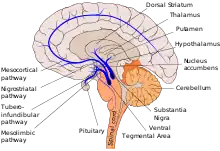

There are five major pathways in the brain connecting other brain areas with the basal ganglia. These are known as the motor, oculo-motor, associative, limbic and orbitofrontal circuits, with names indicating the main projection area of each circuit.[80] All of them are affected in PD, and their disruption explains many of the symptoms of the disease, since these circuits are involved in a wide variety of functions, including movement, attention and learning.[80] Scientifically, the motor circuit has been examined the most intensively.[80]

A particular conceptual model of the motor circuit and its alteration with PD has been of great influence since 1980, although some limitations have been pointed out which have led to modifications.[80] In this model, the basal ganglia normally exert a constant inhibitory influence on a wide range of motor systems, preventing them from becoming active at inappropriate times. When a decision is made to perform a particular action, inhibition is reduced for the required motor system, thereby releasing it for activation. Dopamine acts to facilitate this release of inhibition, so high levels of dopamine function tend to promote motor activity, while low levels of dopamine function, such as occur in PD, demand greater exertions of effort for any given movement. Thus, the net effect of dopamine depletion is to produce hypokinesia, an overall reduction in motor output.[80] Drugs that are used to treat PD, conversely, may produce excessive dopamine activity, allowing motor systems to be activated at inappropriate times and thereby producing dyskinesias.[80]